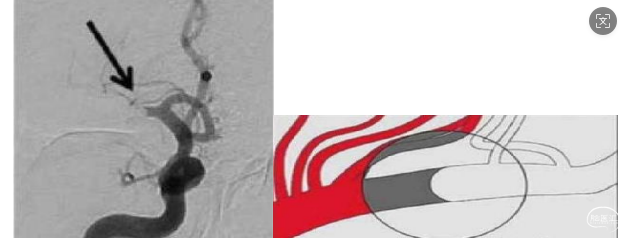

四、刀切征/截断征

术中造影显示造影剂与未显影闭塞动脉支架存在分明的界限,如刀切断端。根据动物实验显示刀切样截断的外观可能为血栓闭塞后血流推挤的水锤效应引起的血块压缩的结果。血栓负荷较大,接触性抽吸比支架取栓更适合。术中选择 ADAPT 直接抽吸取栓。